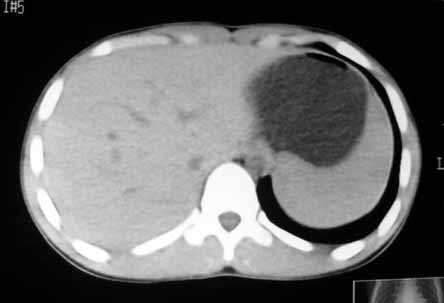

以下是引用zhangzhongshou在2007-5-22 21:04:00的发言:[br]1、脾肿大[br]2、脾脏低密度影,血管瘤?脾梗塞不能除外,建议增强扫描。

以下是引用dyqct在2007-5-22 20:45:00的发言:[br]巨脾,可疑梗塞,建议增强、查血象进一步检查

以下是引用liuyue在2007-5-23 7:57:00的发言:[br]腹主动脉周多个肿大淋巴结,脾大伴三角形低密度影,肠腔积气,考虑:1淋巴瘤2脾大伴梗塞3肠腔积气(肿大淋巴结压迫所致)